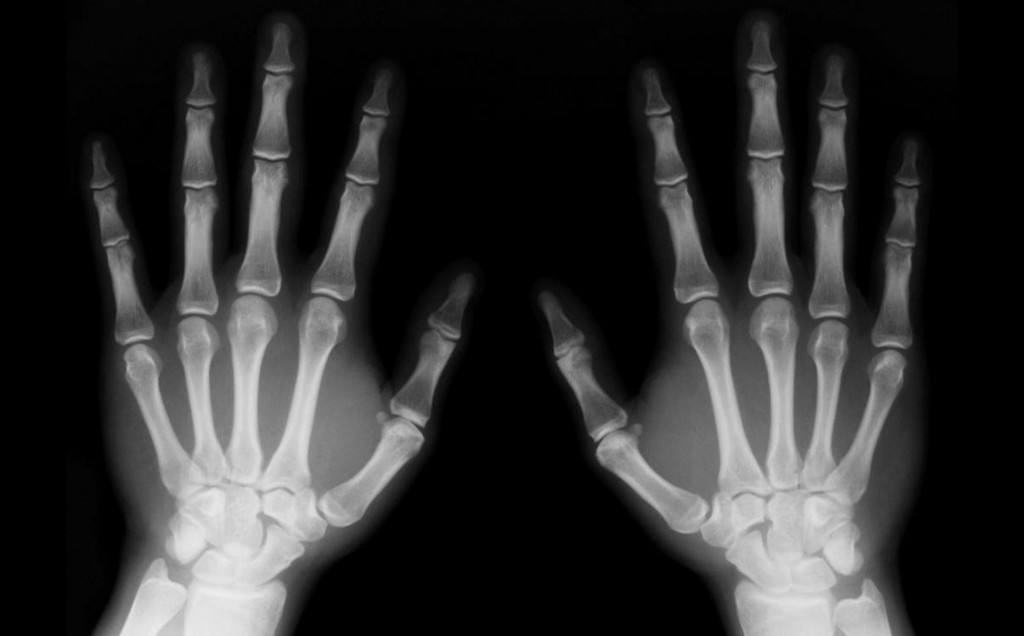

Firma radiografie per creare falso alibi, arrestato medico

Indagini della procura di Firenze su professionista di Savona